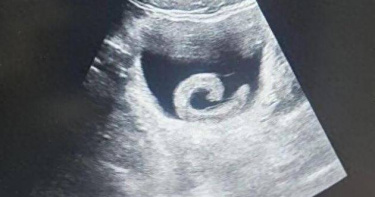

產檢1次多1胎!30歲孕婦懷「同卵四胞胎」 醫驚:機率僅1500萬分之1